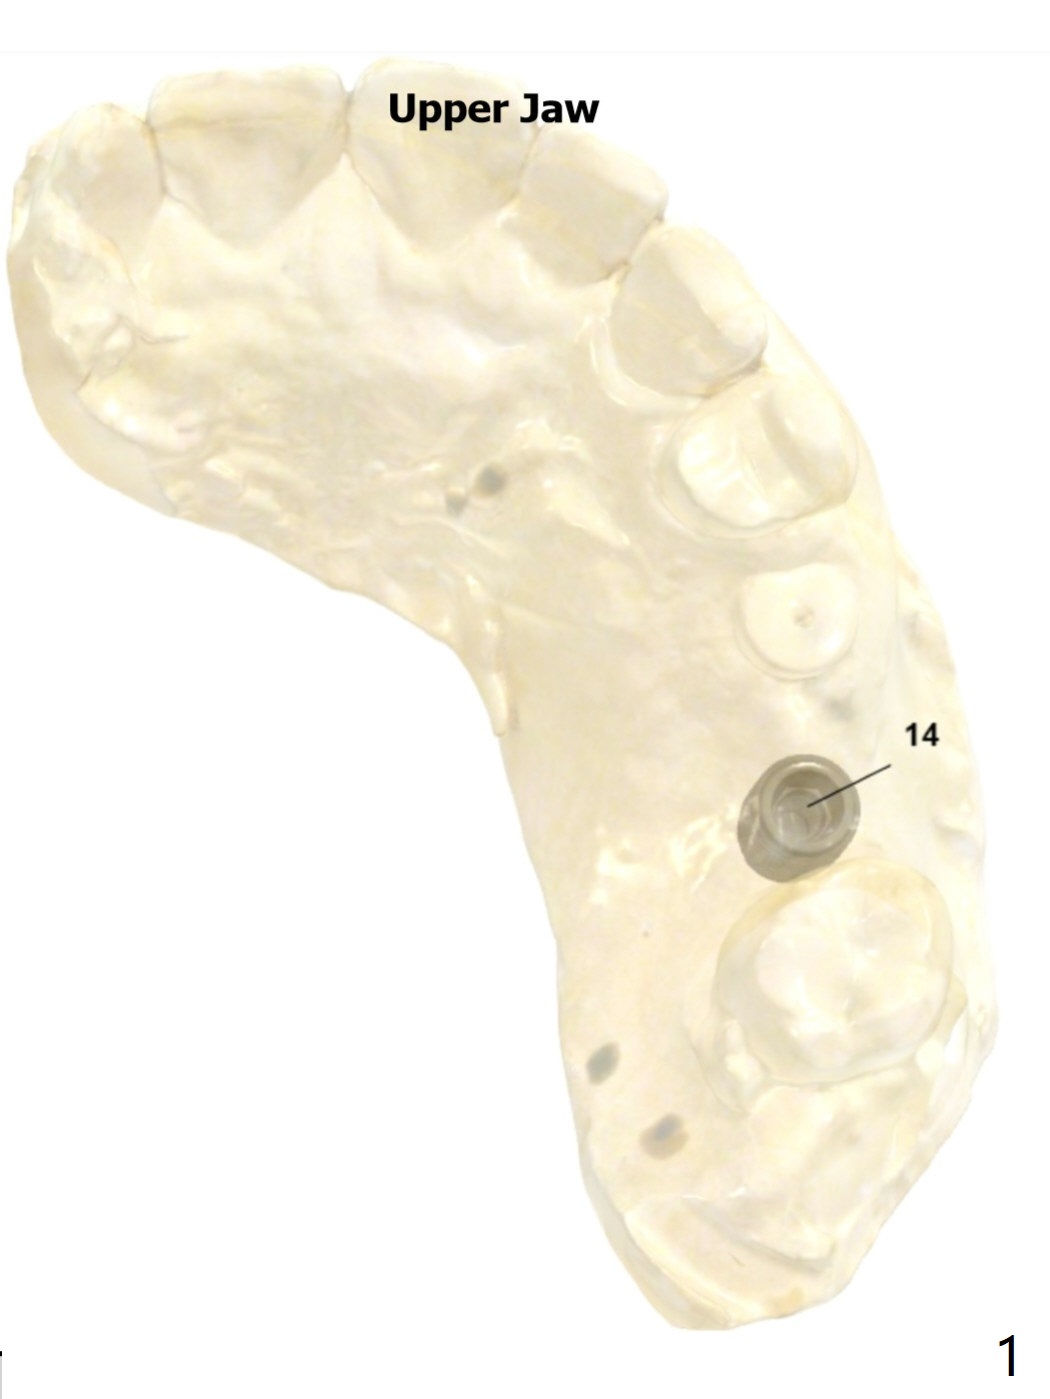

Since bone density is low 3 months post 2nd loss, under drilling, sinus lift for a longer implant (7.3 vs. 10 mm) and PRFx2 are required. One for sinus lift, the other for wound closure (prepare suture). If primary stability is low, no healing abutment is used. Prepare 4 and 4.5x10 dummy implants for sinus lift.